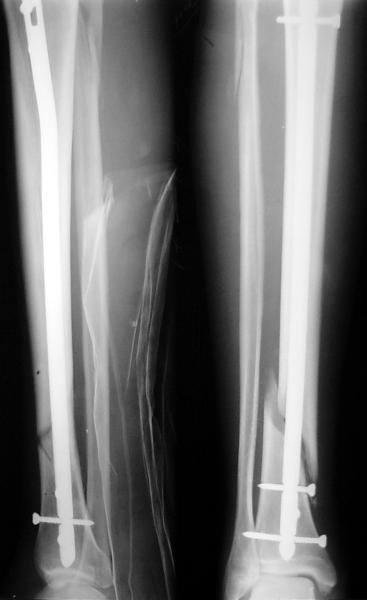

JOM> Вы не послали послеоперационный снимок, поэтому трудно судить о

JOM> состоянии редукции после операции.

А зачем о ней судить - речь ведь не об этом. Мы, помнится, обсуждали возможность ранней нагрузки после остеосинтеза.

JOM> Установка с медиальной стороны гвоздя в области дистального фрагмента

JOM> дополнительного шурупа помогло бы Вам репонировать и удержать перелом

Да, конечно. Но сочли, что и достигнутое положение приемлемо. Тем более, для non-compliant и low demanding пациента.

А если вспомнить лечение аналогичных повреждений функциональными брэйсами (Sarmiento), там рентгенограммы могут быть еще менее привлекательными, однако результаты вполне приемлемы.

JOM> Кстати, если можно пошлите послеоперационный снимок.

Ok. А также и следующий, в 3 месяца.

Это наглядная демонстрация возможности ранней полной нагрузки при нестабильном по оси повреждении, причем не в самых благоприятных механических условиях - при плохом сопоставлении, со слабым фиксатором.

JOM> Ваш больной имеет счастье, что первым согнулся проксимальный

JOM> замыкающий винт, а не дистальный и гвоздь не пенетрировал

Это не счастье, а тонкий инженерный расчет ;-))

Сверху - один статический винт, а снизу - три. Что раньше сломается? Конечно, он потом и нижние сломал, и Вы правы, если бы верхний динамичесий винт уже уперся бы в нижний край отверстия, будь гвоздь подлинее, перфорировал бы сустав как пить дать.

Как я уже говорил, мы сделали выводы из этого и других подобных случаев. Очевидно, решений проблемы два - либо уменьшить нагрузку, либо увеличить прочность фиксатора. Первое решение работает не со всеми больными, так что пошли по второму пути - мы больше не используем гвозди с запирающими винтами диаметром 4 мм.